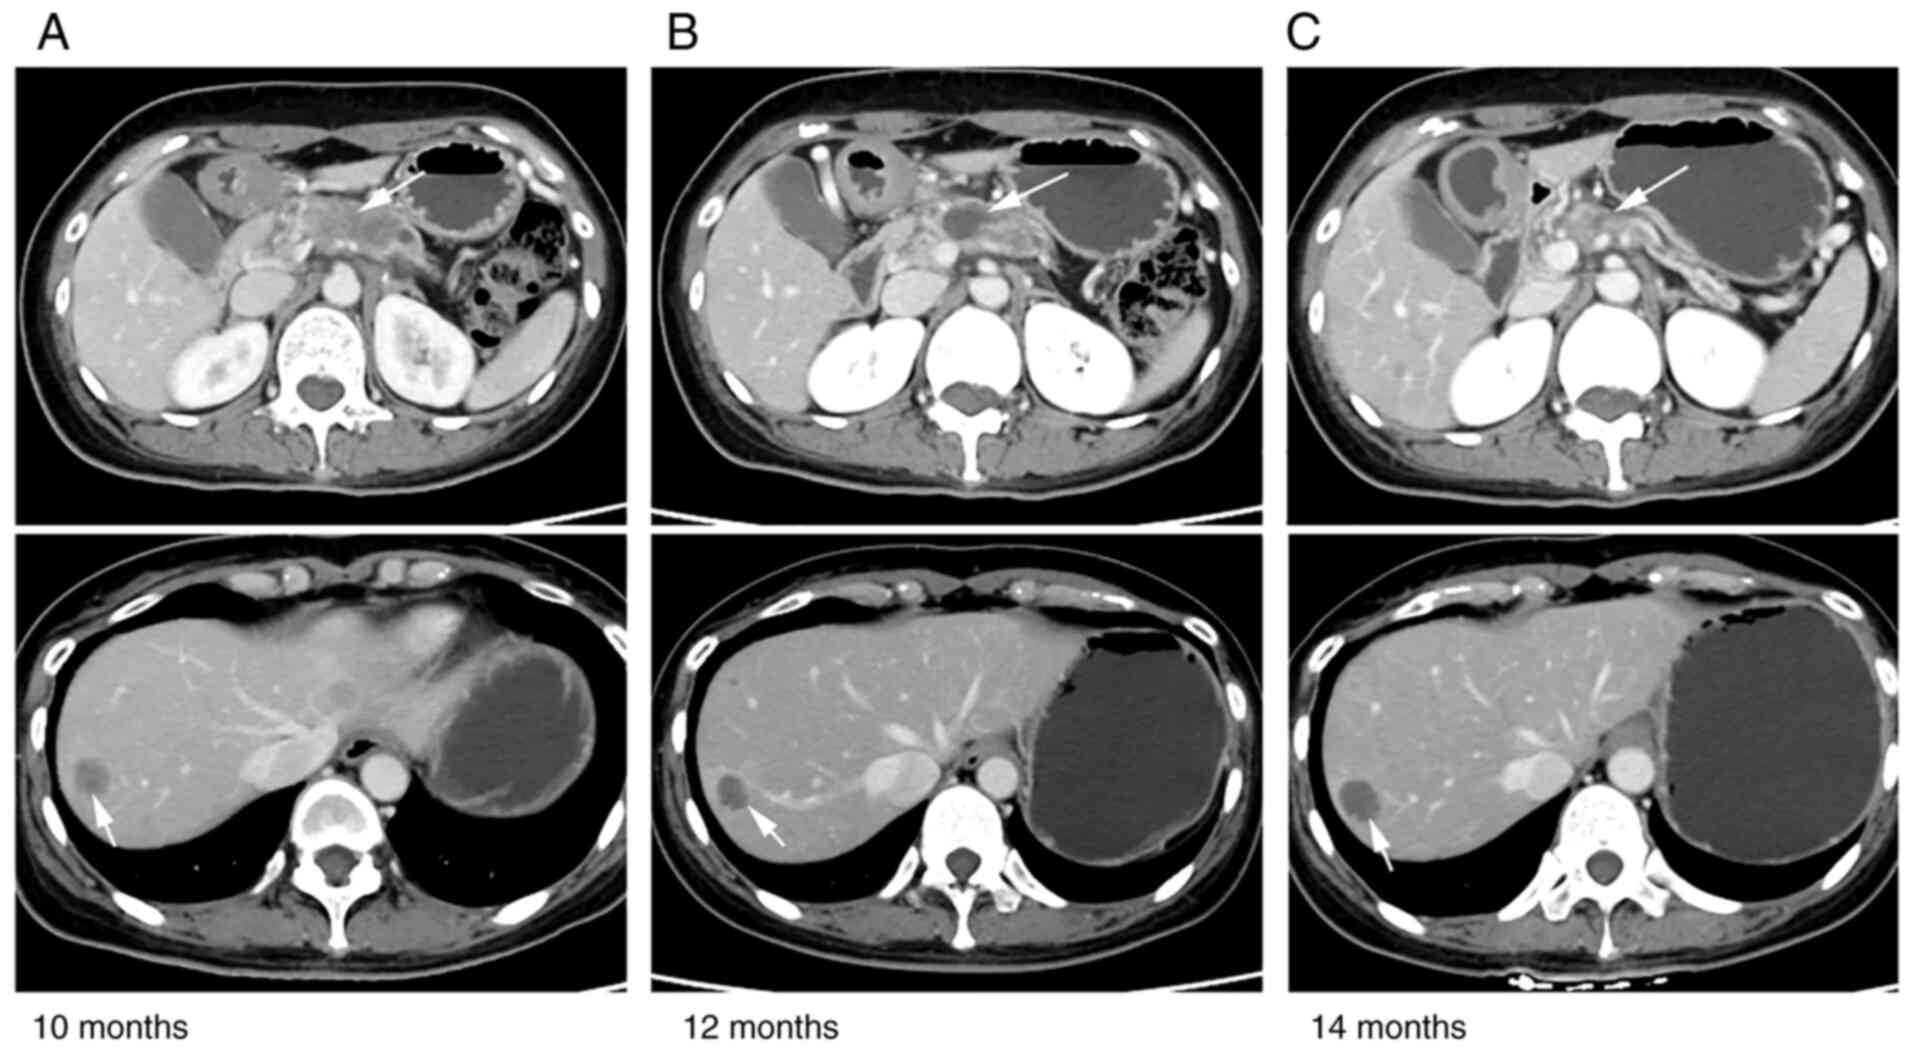

A 42-year-old woman presented with increased levels of serum tumor markers, including carbohydrate antigen (CA)19-9 (3,793 U/ml; normal range, 0–27 U/ml) and carcinoembryonic antigen (CEA; 58.6 ng/ml; normal range, 0–4.7 ng/ml), during a routine physical examination in June 2020, with no obvious symptoms. Enhanced MRI in Renji Hospital (Shanghai, China) 5 days later revealed a mass (49×26 mm) in the pancreatic body and multiple hepatic lesions (Fig. 1A). Next, MRI-guided biopsy of the pancreatic tumor was performed, following which somatic adenocarcinoma of the pancreas was diagnosed. The staging was cT3NxM1, stage IV according to the 8th edition of the American Joint Committee on Cancer for Pancreas and Hepatobiliary Cancers (9). Therefore, the patient was eligible to take part in a single-arm clinical trial assessing the combination of doublet chemotherapy [nab-paclitaxel and gemcitabine (AG)] and the novel PD-1 inhibitor camrelizumab (formerly SHR-1210) for the first-line treatment of metastatic pancreatic carcinoma (ClinicalTrials.gov identifier: NCT04181645; Table I). Therefore, the patient was prescribed first-line immunotherapy treatment of AG + anti-PD-1 immunotherapy 2 weeks after admission for six cycles. The regimen included nab-paclitaxel (Abraxane; 125 mg/m2) and gemcitabine (1,000 mg/m2) on days 1 and 8, along with camrelizumab (200 mg) on day 1 every 3 weeks. Repeat imaging assessment after two and four cycles of this combination treatment revealed a significant reduction in the size of the pancreatic and liver lesions (Fig. 1B). In addition, subsequent MRI scans (Fig. 1C) showed further shrinkage of the tumor and partial response (PR) was concluded using the modified Response Evaluation Criteria in Solid Tumors assessment criteria (Fig. 1) (10). The tumor markers CA19-9 and CEA were restored to the normal ranges. According to the Common Terminology Criteria for Adverse Events (version 4.03) (11), adverse events occurred, which included grade 1–2 rash, edema of the bilateral ankles and eyelids, knee pain, hyperhidrosis and grade 1 anemia. However, no treatment-related grade 3 or 4 adverse events were observed. The patient was next administered six cycles of first-line anti-PD-1 immune maintenance therapy (200 mg camrelizumab on day 1 every 3 weeks) 4 months after admission. After two cycles, a continuous PR was obtained. After the fourth cycle, the pancreatic mass increased slightly in size, and the PR of the liver lesions persisted. The toxicity parameter of transient hyperthyroidism appeared during this period. Afterwards, hypothyroidism was detected, which was controlled by supplementation with levothyroxine sodium tablets (100 µg every day). The progression-free survival (PFS) time from this first-line therapy was 9 months.

Figure 1.

Comparison of abdominal MRI before and after the first-line treatment. MRI images from (A) the time of admission and after first-line treatment at (B) 2 and (C) 3 months post-diagnosis. The pancreatic mass and liver metastases were reduced in size after treatment. Arrows indicate the tumors and lesions.